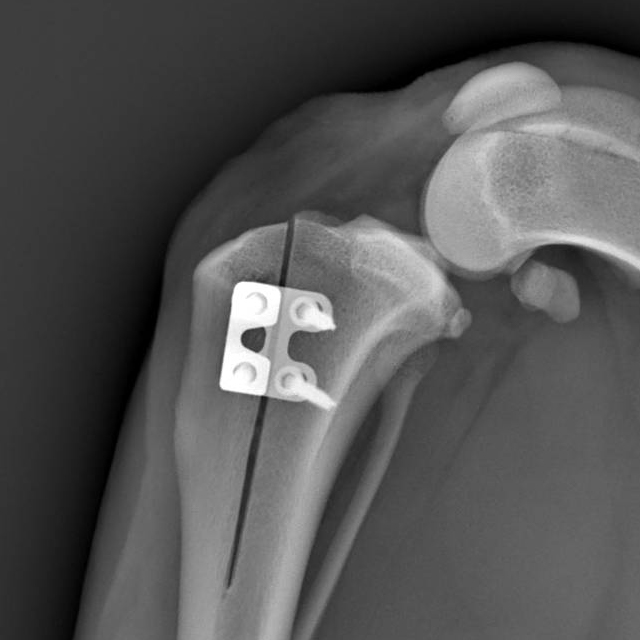

TTA RAPID® X-Ray (Different patient, Post-Op X-Ray courtesy of Dr. Wilhelm)

When the patient suffers from a concomitant patella luxation, which happens to about 20% of small patients with CCL injury, both can be treated with a modified TTA RAPID® procedure and is done by simply adding a RAPID LUXATION Spacer to the TTA RAPID® cage.